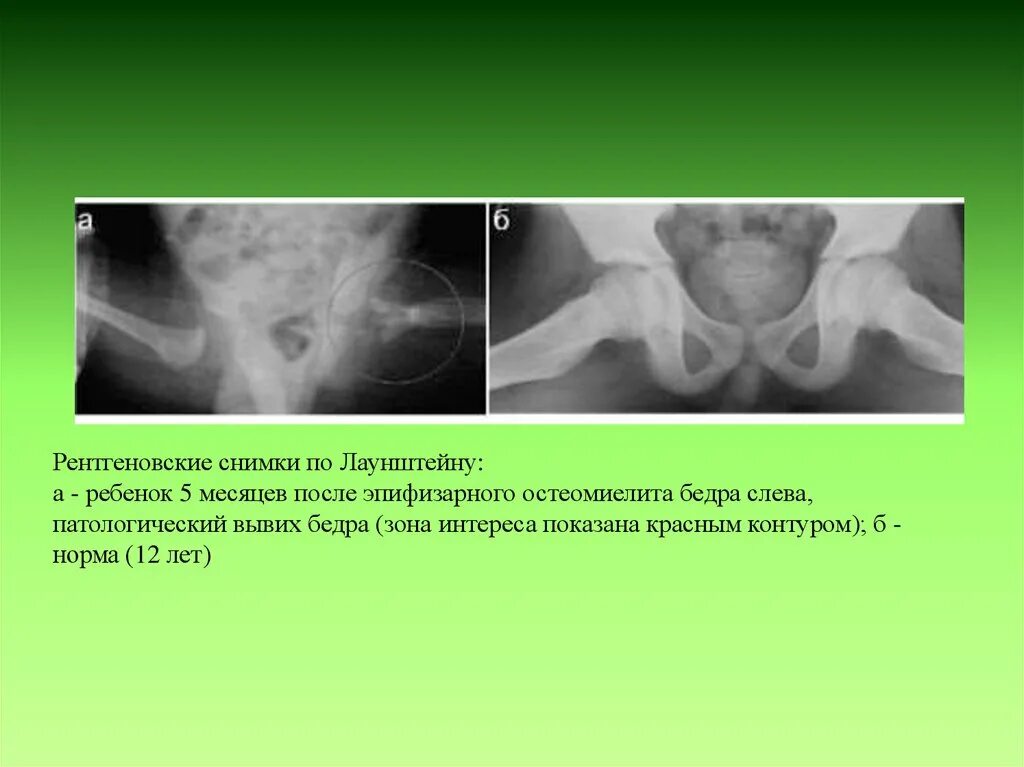

Патологическим называется вывих